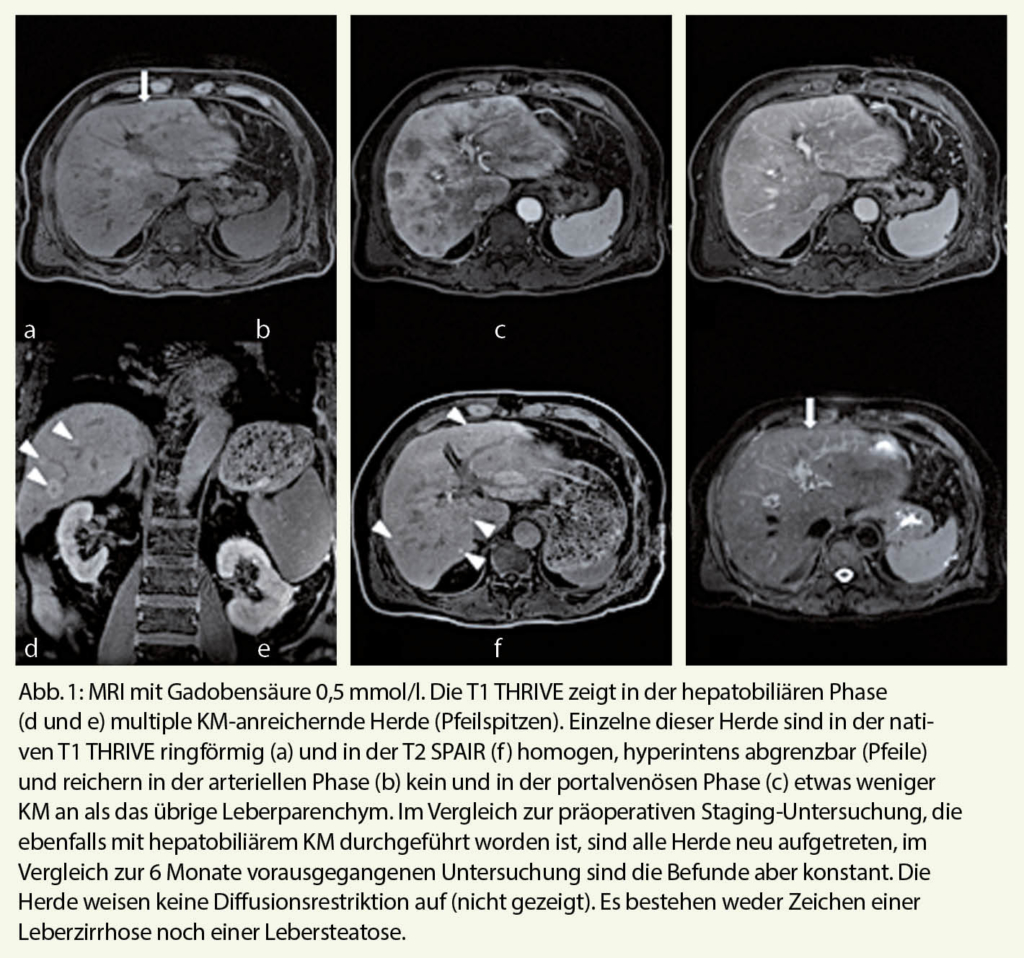

Es handelt sich um einen aktuell 74-jährigen Mann, bei dem knapp 5 Jahre vorher wegen eines Adenokarzinoms des Sigmas, TNM-Stadium pT3 pN1 (2/25) G2, eine erweiterte Rektosigmoidresektion sowie anschliessend eine adjuvante Chemotherapie mit 8 Zyklen Capecitabin und Oxaliplatin durchgeführt worden sind. Bereits unter der Chemotherapie fanden sich leichtgradig erhöhte Leberwerte. In CTs und MRIs konnten im Verlauf Lebermetastasen ausgeschlossen werden. Im MRI zeigten sich aber kleinnoduläre, nicht-neoplastische Veränderungen, die gemäss dem beurteilenden Radiologen gut zu einer nodulär regenerativen Hyperplasie (NRH), möglicherweise als Folge der früheren Oxaliplatin-Therapie, gepasst hätten (Abb. 1). Vor zwei Jahren wurden deshalb und bei anhaltend erhöhten Leberwerten aus mehreren Segmenten der Leber Stanzbiopsien entnommen, die fokal knotig-proliferiertes Leberparenchym mit Verdacht auf Regeneratknoten zeigten. Atrophe Areale fehlten, weshalb eine NRH nicht bewiesen und andererseits eine umschriebene Zirrhose nicht sicher ausgeschlossen werden konnte. Eine weitere histologische Abgrenzung der Veränderungen war nicht möglich. Als dann aber im Verlauf eine progredient sich vergrössernde Milz und ein zunehmender Aszites festgestellt wurden, kam nochmals der Verdacht auf eine Leberzirrhose mit portaler Hypertension auf und der Patient wurde einer erneuten hepatologischen Abklärung zugeführt. Diese war aber widererwarten bezüglich einer relevanten Lebererkrankung, insbesondere einer Leberzirrhose, unauffällig. Es fanden sich normale Leberwerte, eine normale Leberfunktion, fehlende sonographische Hinweise auf eine Leberzirrhose oder eine Pfortaderthrombose sowie ein unauffälliger Fibroscan (Lebersteiffigkeit von 3.7 kPa). Chronische Leberkrankheiten wie eine virale Hepatitis B und C, autoimmune Hepatitis, Stoffwechselstörungen wie Hämochromatose, M. Wilson und einen alpha-1-Antitrypsin-Mangel konnten laborchemisch erneut ausgeschlossen werden. Eine Exposition für Alkohol oder relevante lebertoxische Medikamente gab es mit Ausnahme des Oxaliplatins ebenfalls nicht. Bei Vorliegen einer Eisenmangelanämie veranlasste die Onkologin sowohl eine Gastroskopie als auch Koloskopie, welche einerseits Oesophagusvarizen Grad II und andererseits einen breitbasigen adenomatösen Polypen im Zökum, der die Eisenmangelanämie durchaus erklärte, zu Tage führten. Die Zusammenschau all dieser Befunde führte schliesslich zur Diagnose einer portalen Hypertension, deren Ursache aber nicht in einer Leberzirrhose, sondern in einer sehr wahrscheinlichen Oxaliplatin-induzierten NRH resp. in einer sog. «nicht-zirrhotischen portalen Hypertension» (NZPH) liegt. Unter einer diuretischen Therapie mit Spironolacton kam es zu einer raschen Regredienz des Aszites. Zur Primärprophylaxe einer Oesophagusvarizenblutung wurde eine Therapie mit einem nicht-selektiven Betablocker begonnen.

Fälle mit nicht-zirrhotischer portaler Hypertension (NZPH) im Zusammenhang mit Oxaliplatin-haltigen Chemotherapien bei kolorektalen Karzinomen, für deren Entstehung Oxaliplatin als wahrscheinlichster Faktor befunden worden war, wurden schon vor Jahren beschrieben (2). Die Ursache hierfür ist die Entwicklung einer Medikamenten-induzierten nodulär regenerativen Hyperplasie (NRH), die zu einem sinusoidalen Obstruktionssyndrom (SOS), früher auch venookklusive Erkrankung der Leber genannt, führen kann. Wie Fallbeschreibungen zeigen, können derartige Veränderungen bereits wenige Monate bis mehrere Jahre nach erfolgter Chemotherapie auftreten (2, 3). Die Diagnose wird meistens erst indirekt aufgrund des Vorhandenseins von Zeichen der portalen Hypertension wie Splenomegalie, Aszites und Oesophagusvarizen in Abwesenheit einer Leberzirrhose gestellt. Typischerweise finden sich bei diesen Patienten in aller Regel normale Leberwerte und insbesondere eine normale Leberfunktion. Sehr oft – in fast 50% der Fälle – können nach Oxaliplatin-basierten Chemotherapien bei Patienten mit metastasierendem kolorektalem Karzinom und Hepatektomie mikrovaskuläre, sinusoidale Leberveränderungen gefunden werden (4, 5). Der histologische Nachweis einer NRH ist aber meist schwierig und gelingt in der Minderzahl der Fälle, wie zum Beispiel eine Studie bei 6-Thioguanine-assoziierten NRH gezeigt hat (6). Radiologisch finden sich bei Oxaliplatin-induzierten Leberschäden meist diffuse oder retikuläre Signalveränderungen in Kontrastmittel-(KM-)verstärkten MR-Aufnahmen (7). Wahrscheinlich eher seltener können sich diese Leberschäden auch als fokale Läsionen bemerkbar machen (8, 9). NRH werden im Gegensatz zu Metastasen und normaler Leber nur durch das Pfortadersystem mit Blut versorgt. Bei Verwendung interstitieller KM gibt es deshalb Überschneidungen mit hypovaskulären Metastasen. Zuverlässig gelingt die Unterscheidung von NRH und Metastasen im MRI jedoch mit hepatobiliären KM: In der dynamischen CT- oder MR-Bildgebung ist die NRH in der arteriellen Phase verglichen zum umgebenden Lebergewebe hypodens/hypointens, in der portalvenösen Phase leicht bis mässig hypodens/hypointens und in der Equilibriumphase isodens/isointens. Sie speichert hepatobiliäre KM, wobei die zentrale Portion typischerweise eine relative Hypointensität aufweist (sog. «donut sign»). Dies korreliert zu zentralen Portalgefässen und umgebenden hyperplastischen Hepatozyten (10). Über den Stellenwert der PET-CT zur Unterscheidung von NRH und Metastasen gibt es keine Untersuchungen. Bei unklaren Fällen muss die Differenzialdiagnose von entzündlicher versus maligner Läsion durch die gezielte Biopsie geklärt werden, wie das auch bei unserem Patienten der Fall war. Zum nicht-invasiven Ausschluss einer Zirrhose könnte – wie unser Fall auch zeigt – ein Fibroscan hilfreich werden.